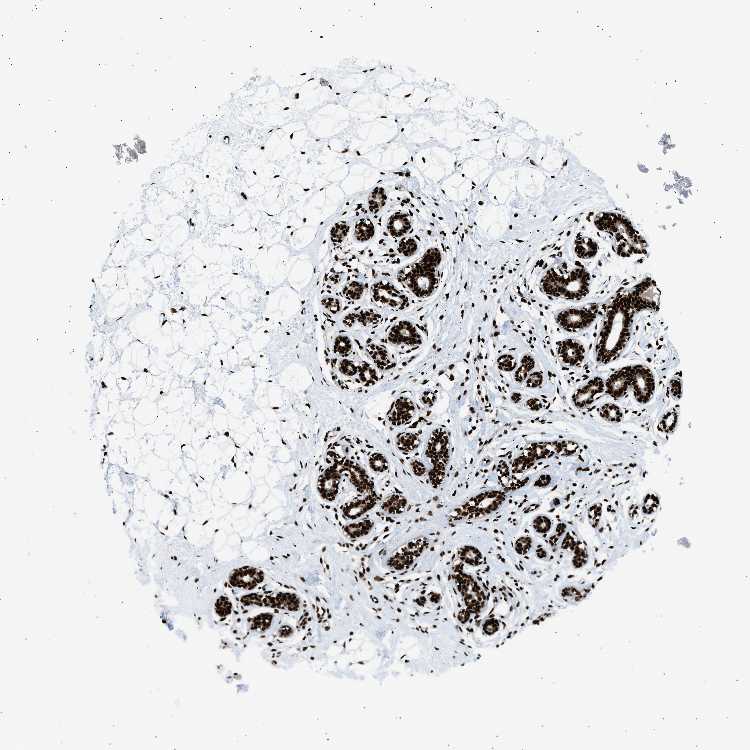

BREAST - Antibody stainingi

Antibody staining in the annotated cell types in the current human tissue is reported as not detected, low, medium, or high, based on conventional immunohistochemistry profiling in selected tissues. This score is based on the combination of the staining intensity and fraction of stained cells.

Each image is clickable and will lead to virtual microscopy that enables deeper exploration of all samples and also displays staining intensity scores, fraction scores and subcellular localization as well as patient and tissue information for each sample.

Antibody HPA007644Antibody CAB004435Antibody CAB016225

Adipocytes MediumHighHigh

Glandular cells HighHighHigh

Myoepithelial cells HighHighHigh